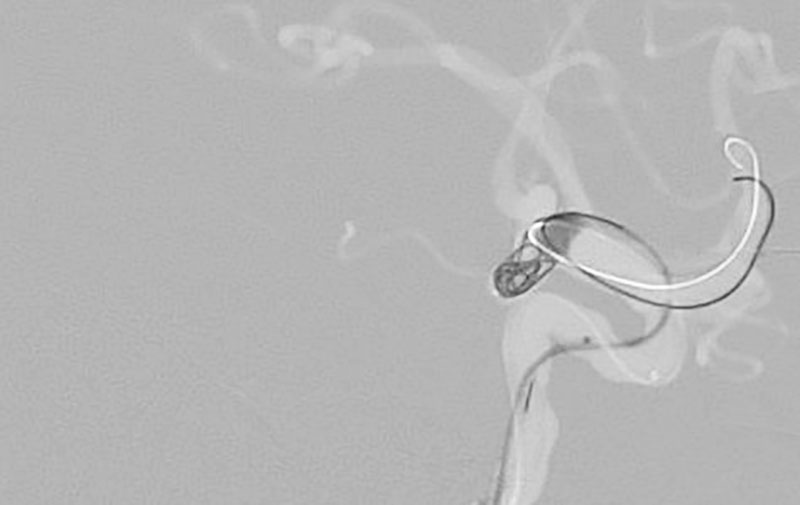

No.1631 手術後